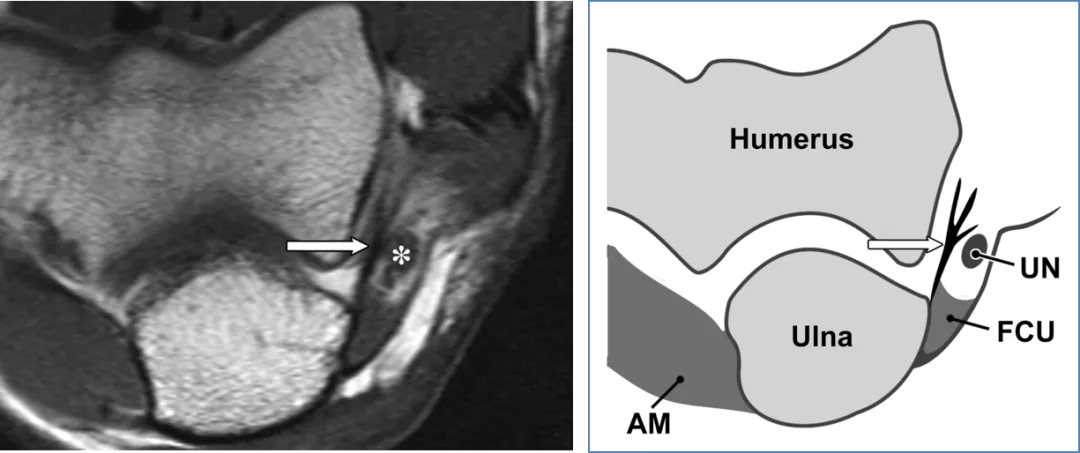

尺神经解剖及示意图:

a)33 岁女性受试者的横轴位 T1 加权磁共振成像,以及(b)对应的示意图,均清晰显示尺侧副韧带后束(箭头所示)和尺神经(图 a 中星号标注,缩写为 UN)。图中 AM 代表肘肌,FCU 代表尺侧腕屈肌。